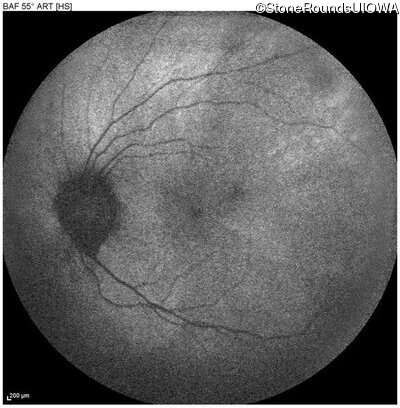

Blue Autofluorescence - Left - 20/20 -1

Exemplar